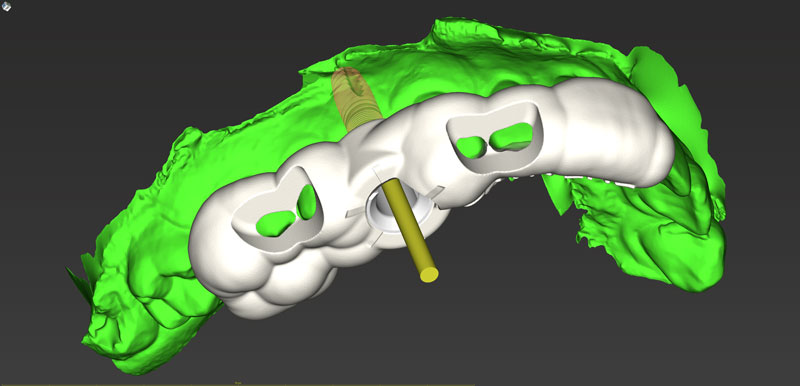

Ψηφιακό πλάνο θεραπείας

Κατευθυνόμενη τοποθέτηση εμφυτευμάτων

Είδη και ακρίβεια χειρουργικού οδηγού

Σχεδιασμός χειρουργικού οδηγού

- Ψηφιακό πλάνο θεραπείας

- Κατευθυνόμενη τοποθέτηση εμφυτευμάτων

- Είδη και ακρίβεια χειρουργικού οδηγού

- Σχεδιασμός χειρουργικού οδηγού